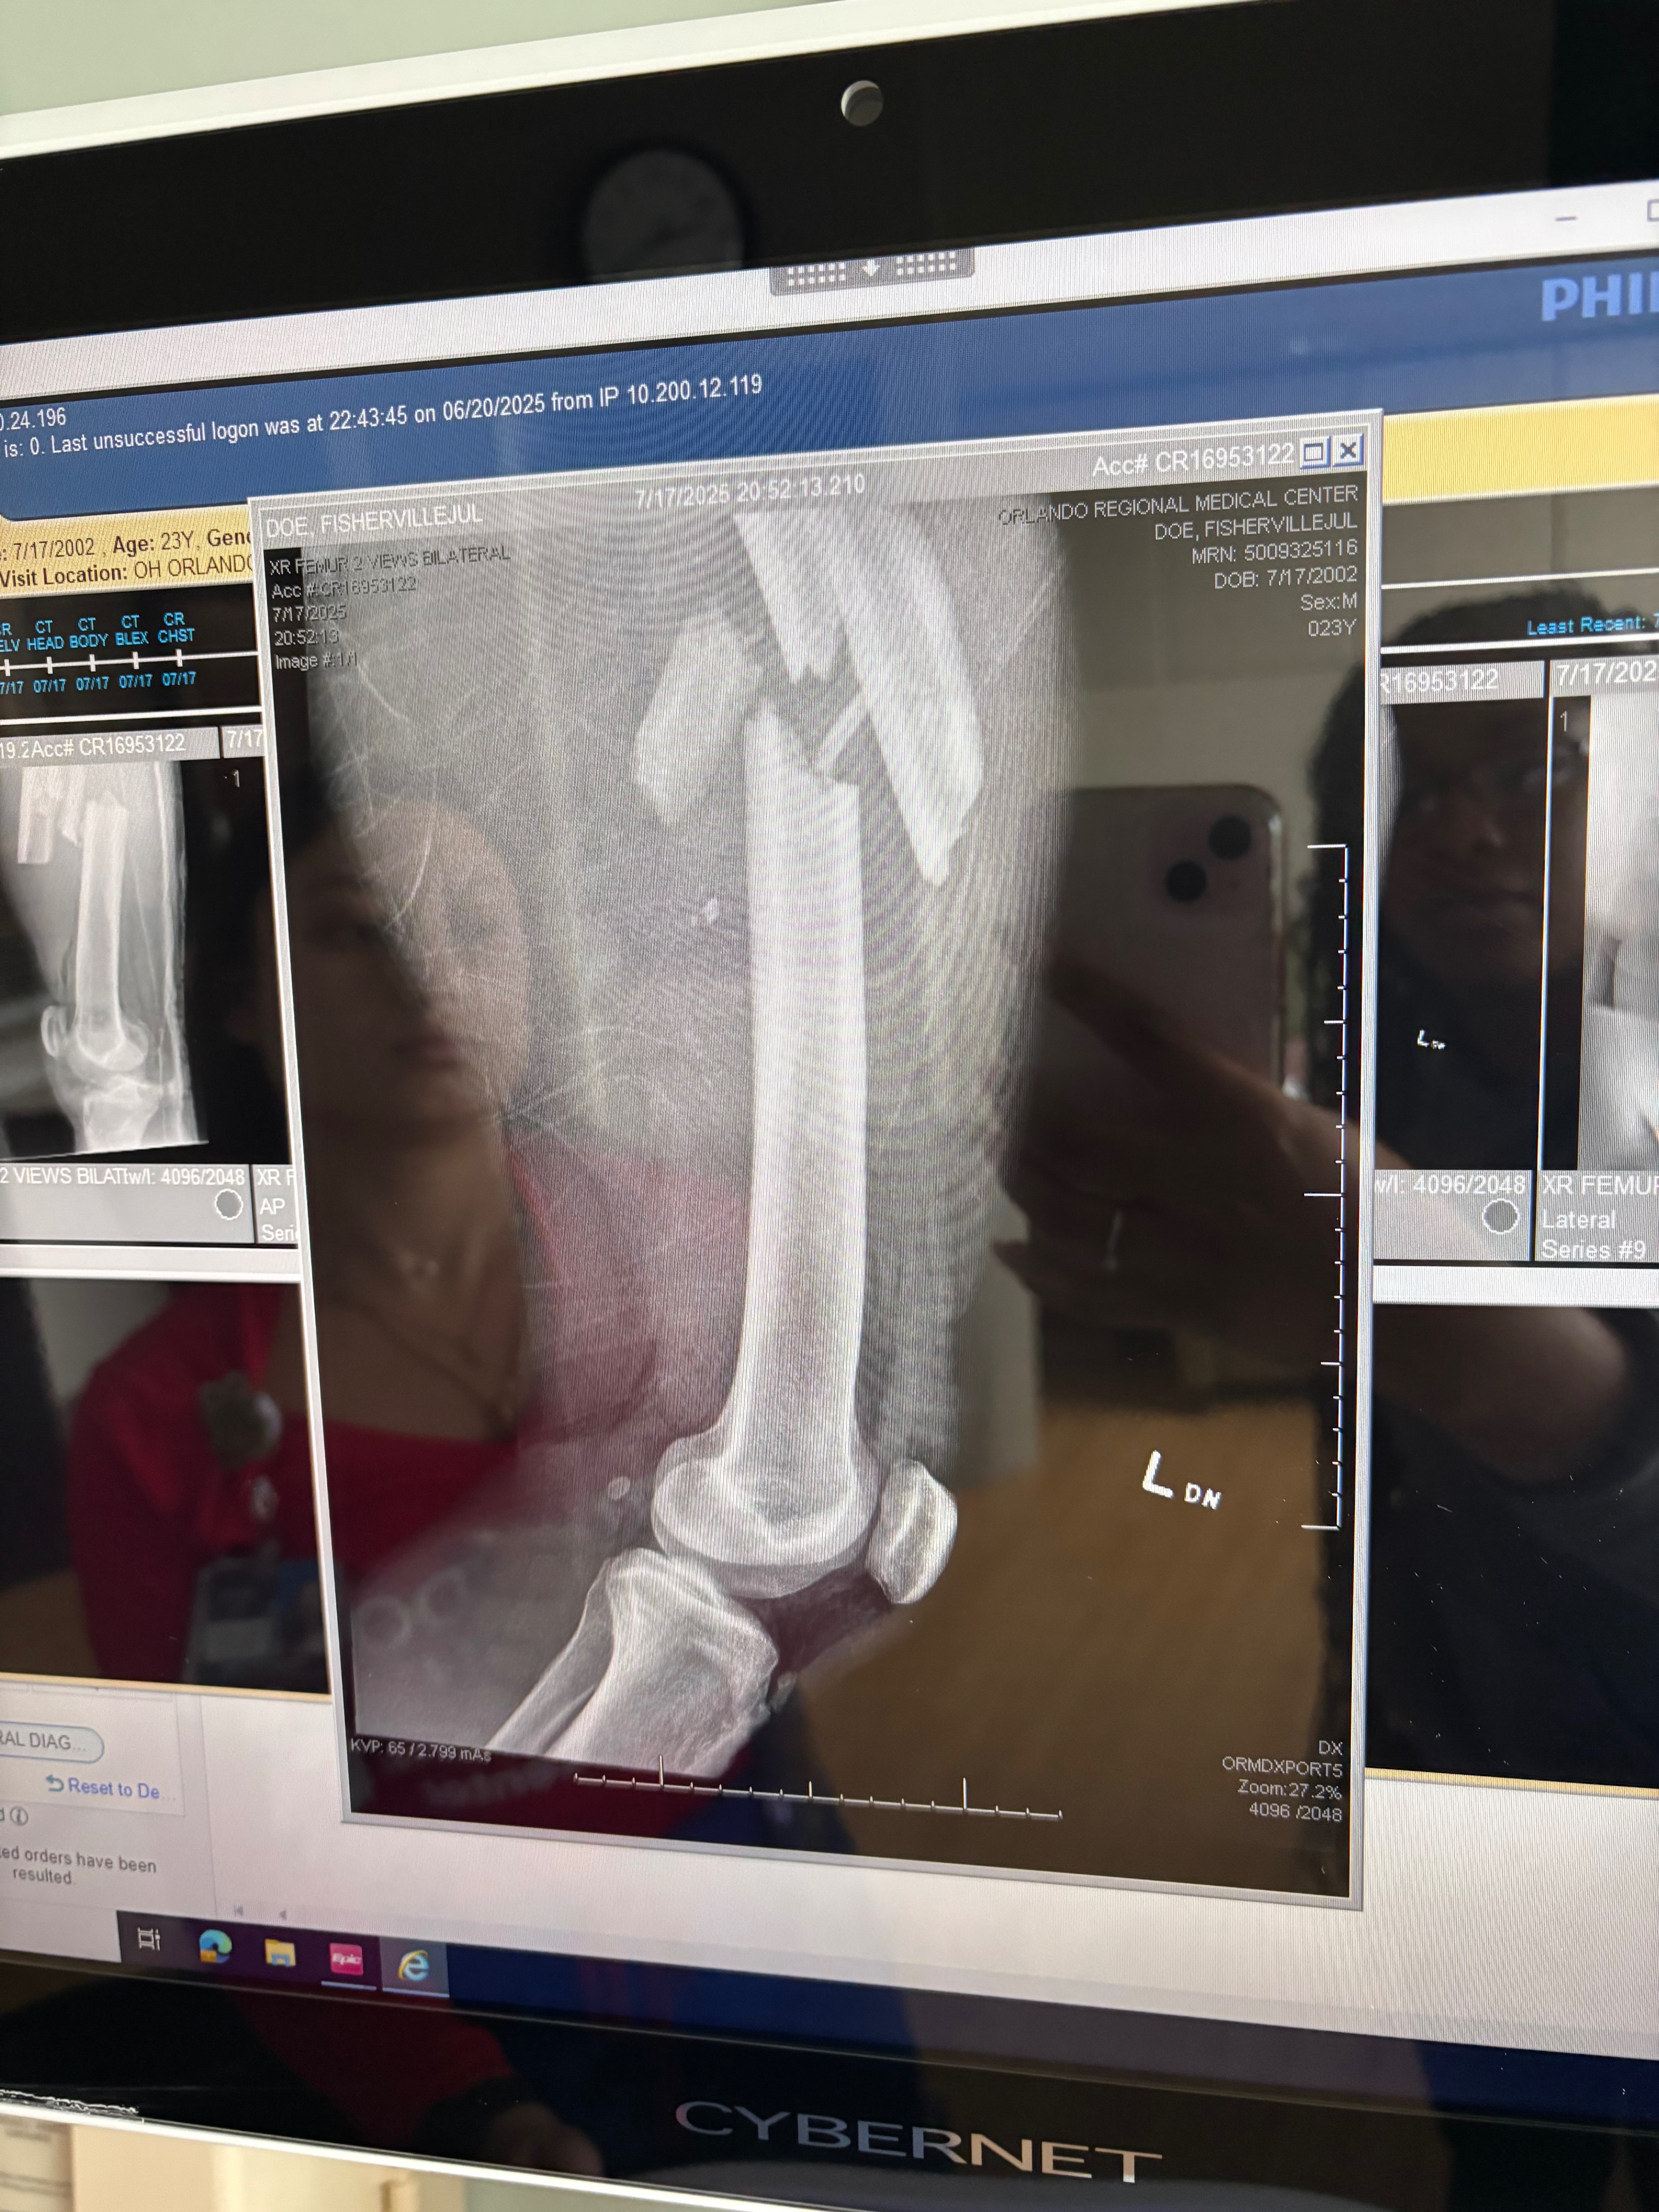

I was rushed to the hospital, in an ambulance and they immediately began working on me. The doctors told me both of my femurs and my shin were shattered and that I have multiple other injuries, and this is just the beginning. I’ll need more surgeries, months of physical therapy, and help doing even the most basic things.